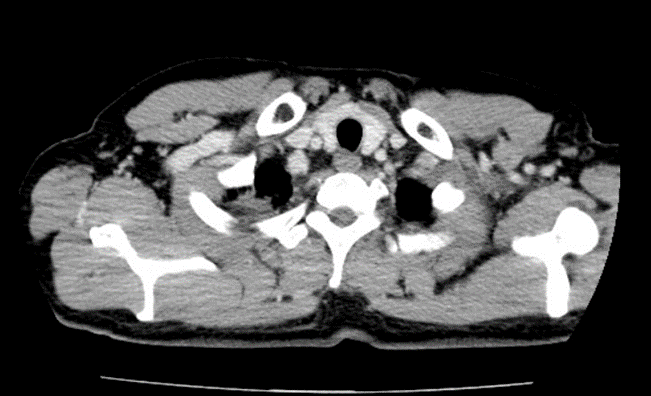

Chụp cắt lớp vi tính lồng ngực sau điều trị: Hình ảnh khối u thùy trên phổi phải kích thước 3×2 cm

Sau điều trị 6 tháng: Hình ảnh khối u thùy trên phổi phải kích thước 3×2 cm

Sau điều trị 9 tháng:

Hình ảnh khối u thùy trên phổi phải kích thước 1×2 cm.